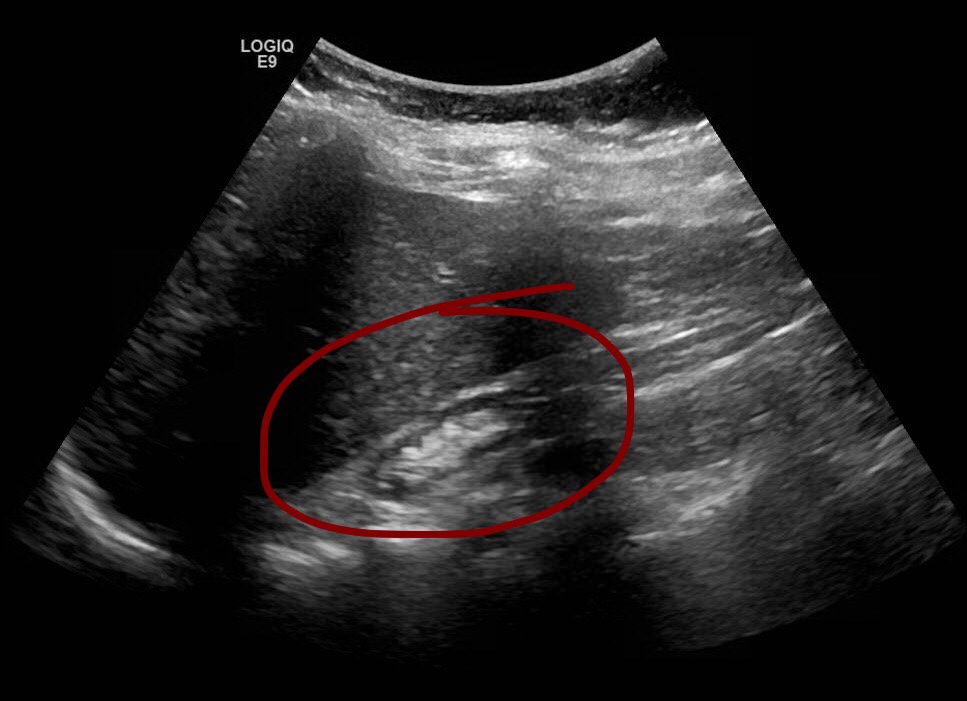

In full sized adults you’ll observe the kidney in the right iliac fossa. Image the kidney in sagittal and transverse planes. Utilize Doppler to see the vascularity. Measure the kidney. If the kidney is too large you can take a panoramic image. Make sure to take not of the echogenicity, check for edema, areas of no vascularity, look for collections.